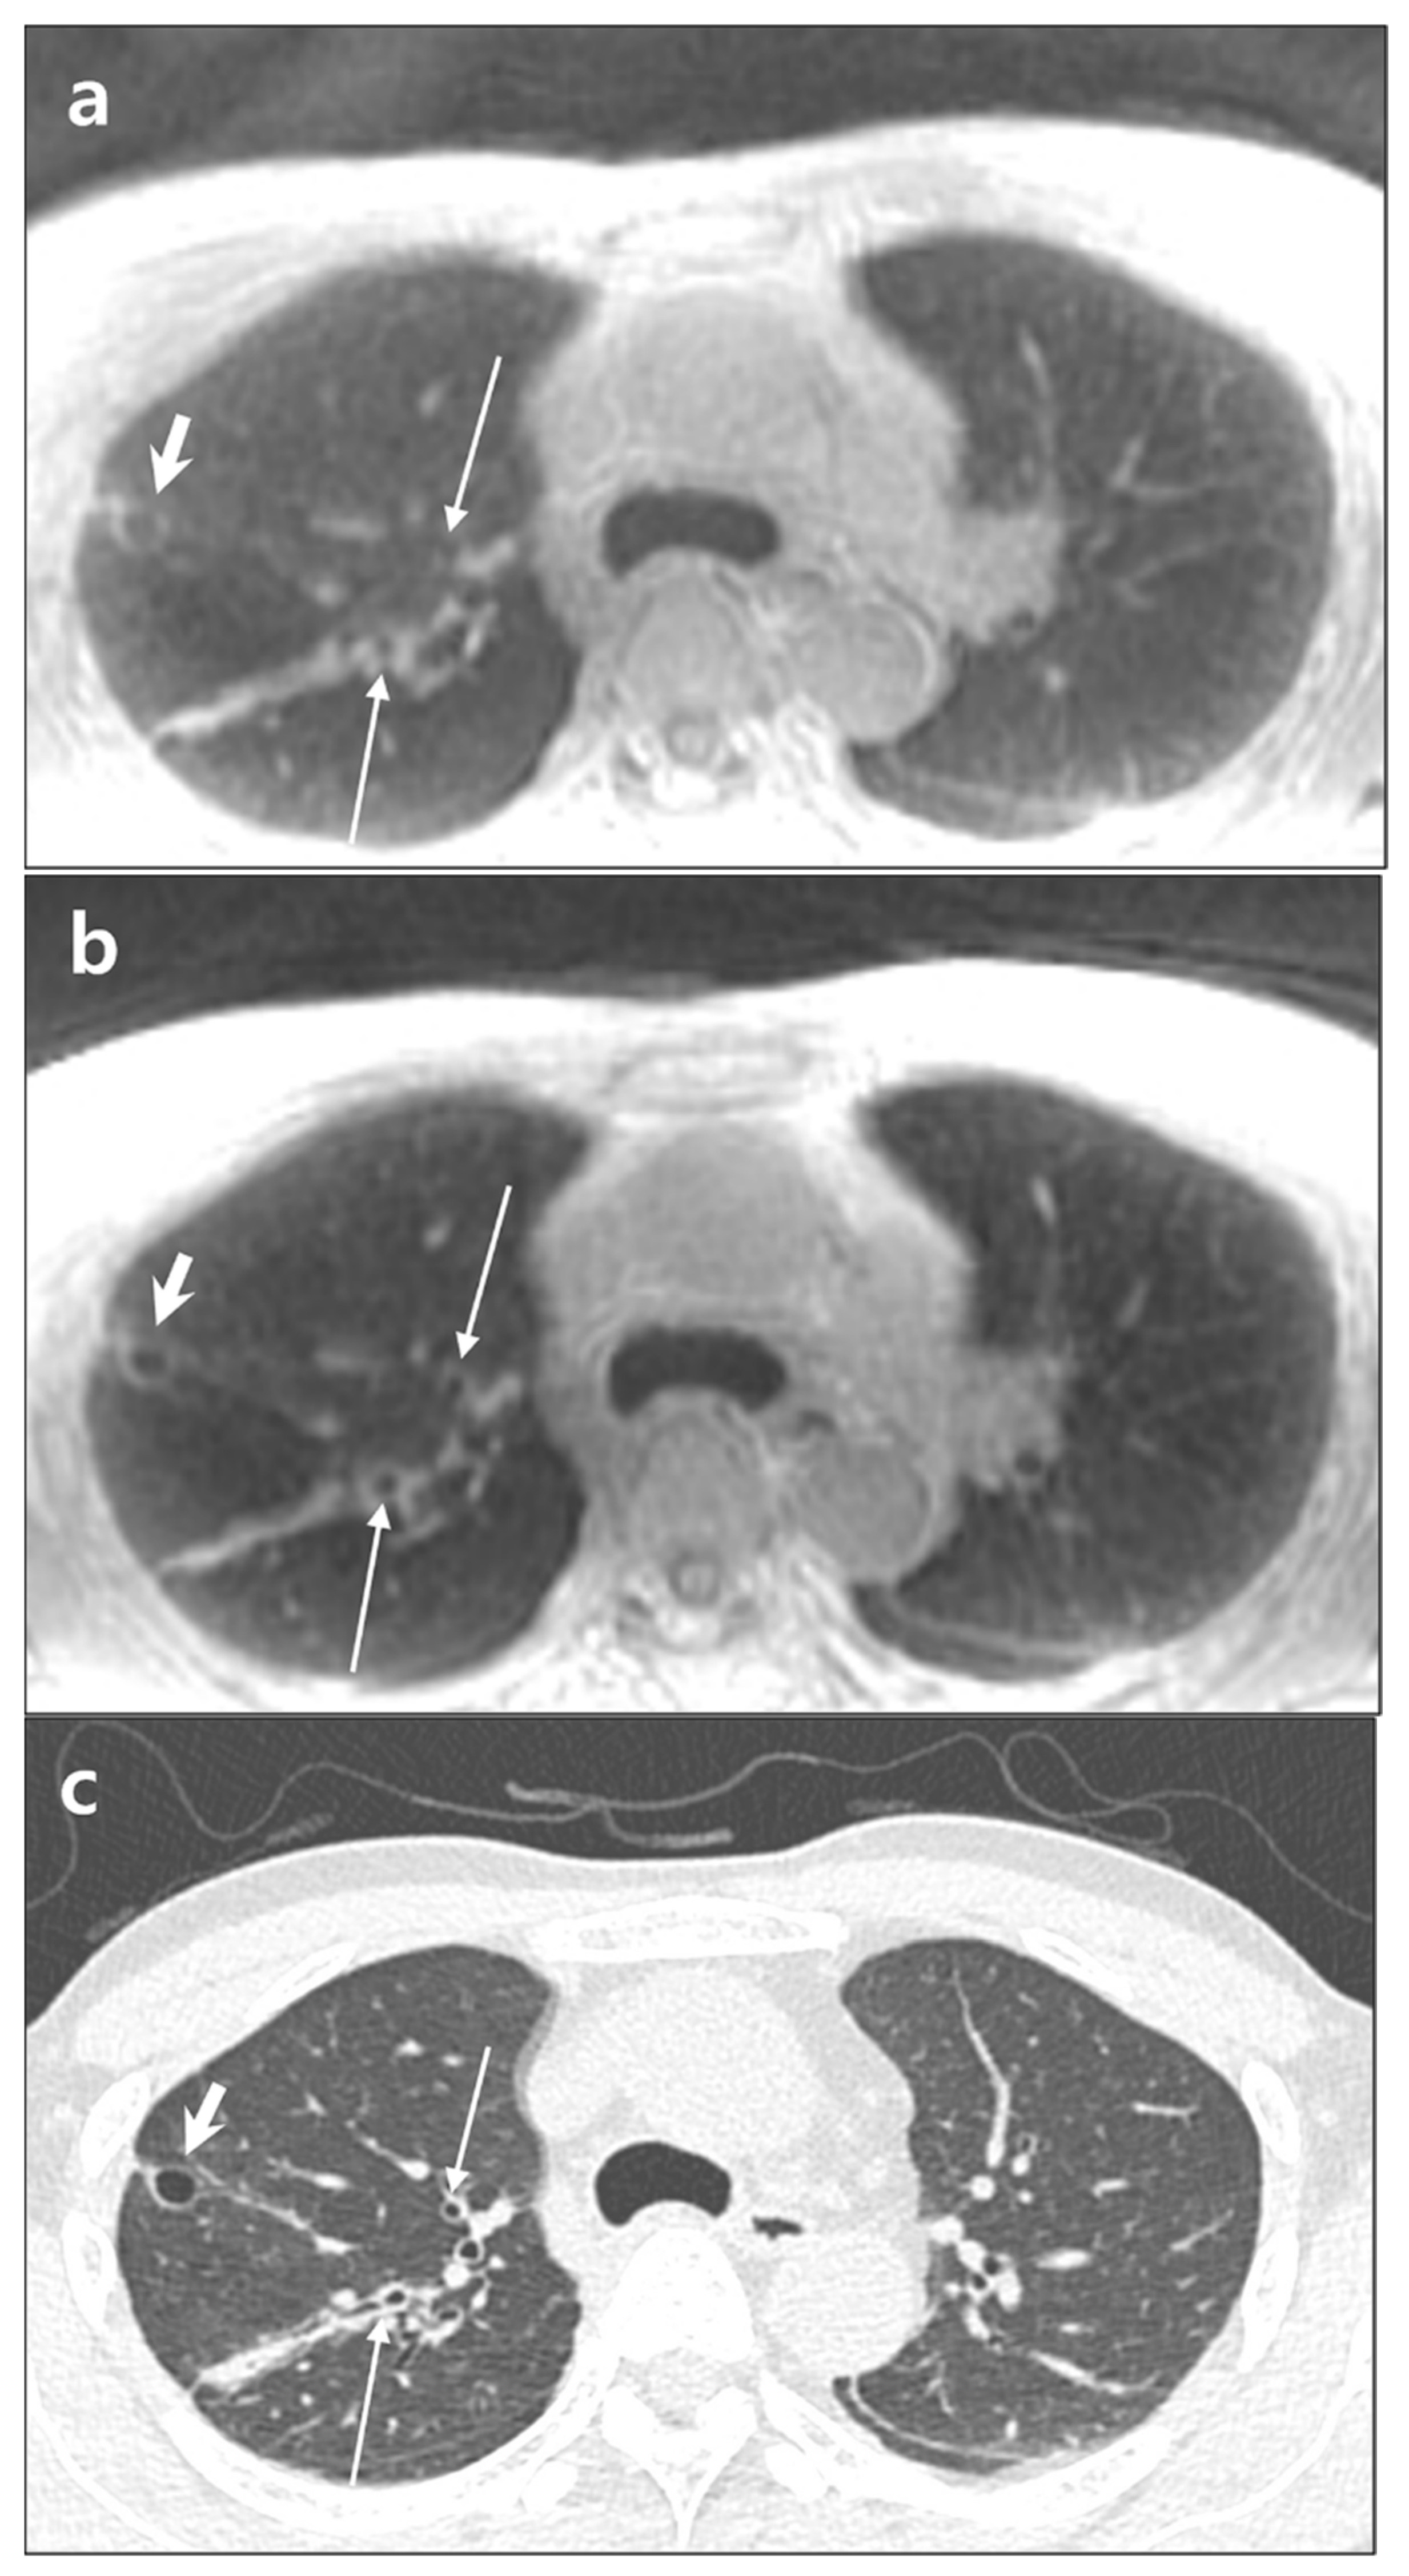

3.3. Lesion Detection